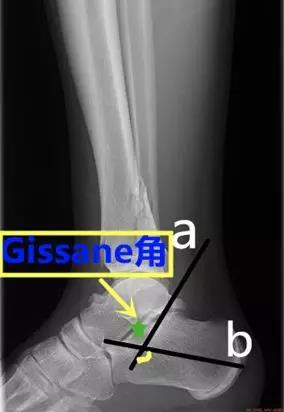

- Gissane角:从跟骰关节面连线与后关节面后缘连线 的夹角。

- 正常值为:120°~145°。

- 临床意义:跟骨骨折时角度可能会发生变化,该角度提示前中后关节的关系。